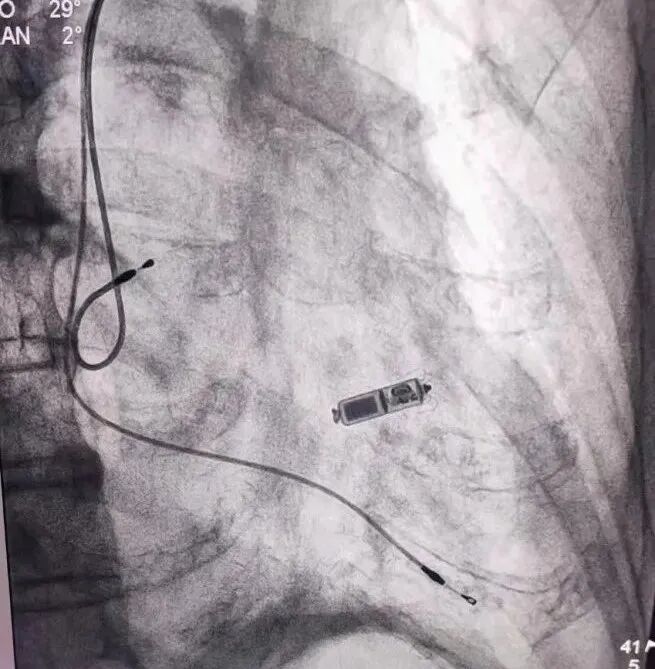

▲图丨手术进行中

手术当天,在局部麻醉的情况下,买买提艾力主任通过股静脉穿刺,将起搏器通过导管顺利植入到患者心腔内部。在整个过程中患者始终保持清醒状态,约40分钟后手术顺利完成。术后6小时患者恢复正常的活动,目前已康复出院。